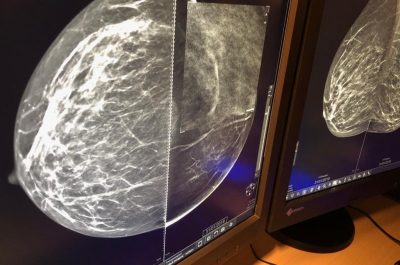

Mammografia 3 D, scoprire i tumori “invisibili”: ecco come funziona e quando è necessaria la tomosintesi